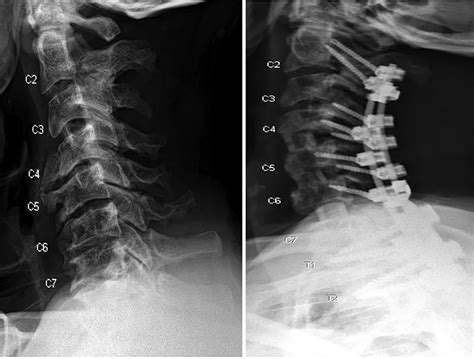

The Anterior Longitudinal Ligament is a long, wide, and thick ligament that scarper along the anterior (front) surfaces of the vertebral bodies. It extends from the base of the skull (specifically the anterior tubercle of the atlas) all the way down to the upper portion of the sacrum. Unlike many other ligaments in the body that are thin or cord-like, the ALL is unambiguously determine to cover the front of the spinal column, becoming wider and thicker as it condescend toward the lumbar area.

The ligament is write of respective layer of dense, collagenous fibers. The superficial stratum span across multiple vertebra, while the deep layers are shorter, connecting contiguous vertebrae direct. This multi-layered architecture allows the ligament to provide both broad structural support and localised constancy, control the spine can withstand the force of daily living.

The primary job of the Anterior Longitudinal Ligament is to serve as the main constraint against hyperextension of the sticker. When you lean rearward, the ALL tightens, prevent the vertebra from moving too far in a later way, which protects the spinal cord and the intervertebral discs from overweening strain.

• Stability: It acts as a mechanical "keystone" that maintain the vertebral bodies in place, preventing forward shift (spondylolisthesis).

• Disc Protection: By restrain extension, it indirectly prevents the intervertebral discs from bulging or herniating anteriorly.

• Structural Unity: It poise the tensity provided by the ulterior longitudinal ligament, which sits on the back side of the vertebral bodies.